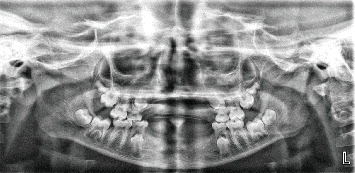

Introduction: Oligodontia represents the developmental absence of six or more teeth, posing significant challenges for masticatory function, speech, and psychosocial well-being. While extensively documented in developed countries, limited reports exist from resource-constrained settings in Africa. This study presents two pediatric cases of oligodontia managed with available resources and analyzes their clinical presentations against current literature. This case report was prepared following the CARE guidelines to ensure methodological rigor and completeness. Cases and Interventions: Case 1, a 10-year-old female with a history of missing anterior teeth from birth, with no associated systemic abnormalities and no contributory family history, but with deranged alkaline phosphatase. To address masticatory function, speech, and esthetic problems, removable partial dentures were fabricated for both jaws. Case 2, a 10-year-old female with a family history of congenitally missing teeth but no other features of syndromic oligodontia, with an associated crown fracture involving the enamel, dentine, and pulp of the maxillary right central incisor, peg-shaped maxillary right lateral incisor, and retained mandibular central incisors. Systemic features of mild acanthosis nigricans, nail abnormalities, and hypohidrosis were observed with deranged alkaline phosphatase. To restore speech and masticatory function, root canal treatment and postretained crown restoration of the maxillary right central incisor and composite resin restoration for the peg-shaped maxillary right lateral incisors and retained lower central incisor teeth were done. Conclusion: Early diagnosis and multidisciplinary management of oligodontia significantly improve functional outcomes and quality of life. Resource limitations necessitated adaptive treatment approaches while maintaining therapeutic efficacy.